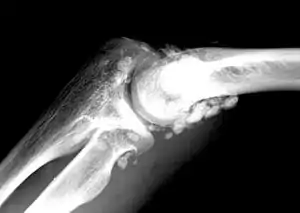

X-ray of an elbow affected by synovial chondromatosis

In the early stages of the disease it is often confused with tendinitis and/or arthritis. Once it reaches transitional the loose bodies become apparent with X-ray in greater than 70% of cases, with MRI often showing where xray fails. In experienced hands, ultrasound is also useful for the diagnosis.[2]